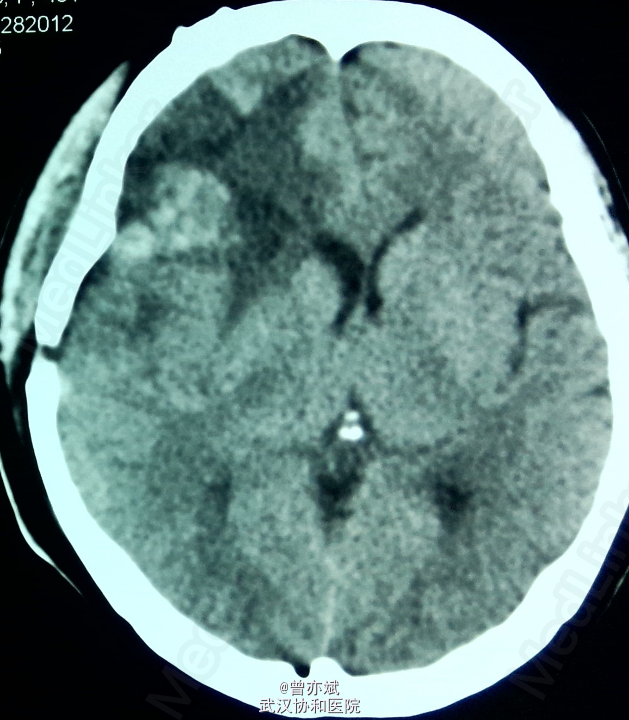

查体除左侧肢体肌力稍差4+,余无阳性体征。MRI如下

术后CT如下